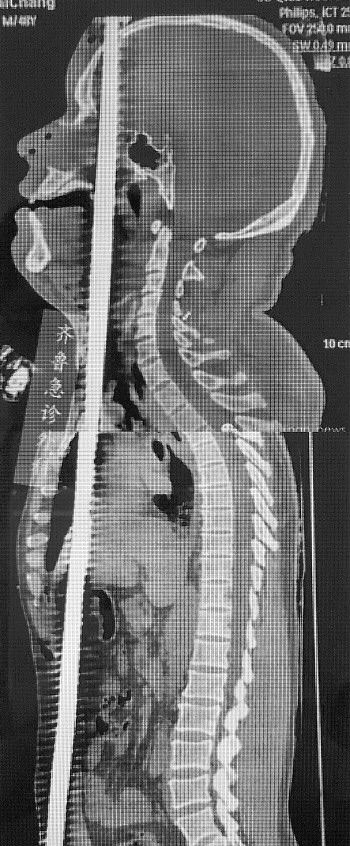

近日,山东大学齐鲁医院急诊夜班收治一名正中贯通伤患者,钢筋自头顶而入,纵穿整个躯干,更加神奇的是,钢筋成功避开体内几乎所有重要脏器。

6月14日下午4点,山东大学齐鲁医院急诊收治了一名正中贯通伤患者,该患者高空作业时从5米高空坠落,地上正好有一竖起的钢筋,钢筋从男子的阴部直穿头顶。经过7个多小时的手术,钢筋被顺利取出,测量长度约150厘米。

因钢筋贯穿了男子的泌尿、腹部、胸部、口腔、鼻腔、脑部等部位,医院急诊外科、神经外科、口腔科、耳鼻喉科、胸外科、心外科、泌尿外科等多科室专家联合对男子进行会诊。

经检查发现,该男子意识清楚,鼻腔口腔有鲜血流出。钢筋从男子的右阴囊插入,途径泌尿系统,伤及腹部的肝脾,紧贴心脏和颈动脉贯穿而过。从咽喉直插入口腔,舌头,上颚经鼻腔,插入大脑,最后钢筋从头顶穿出。

6月14日15:00近2米长钢筋从下体直穿头顶

14日15:00许,济南长清一工地,一名中年男子从5米高空坠落,地上正好有一竖起的钢筋,这根近2米长、粗约1.5厘米的钢筋从男子的阴部直穿头顶,阴部以下露出长约40厘米的钢筋,头顶上穿出长约50厘米的钢筋,男子下体和脸部都有鲜血,场面触目惊心。

短暂的交流使桑锡光心里有了数,检查发现,钢筋从男子的右阴囊插入,途经泌尿系统,伤及腹部的肝脏,紧贴颈动脉贯穿而过。从咽喉直插入口腔,伤及舌头,从上颚经鼻腔,插入大脑,钢筋从头顶穿出。

患者被送到医院时,头部和下体外露的钢筋太长,妨碍医生手术。无奈之下医生联系了消防部门,济南消防泉城中队的消防队员赶到现场后,和医生开始协商救援方案。由于钢筋纵向贯穿男子全身,医护人员对钢筋在男子体内的位置做了详细检查之后,发现钢筋擦心而过。